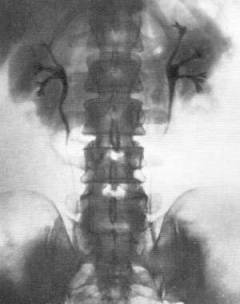

- Экскреторная урография. Введение контрастного вещества, выводимого почками, позволяет наблюдать за кровообращением в почках и оценивать функцию фильтрации и концентрации мочи. Наличие препятствия приводит к задержке вещества на уровне окклюзии.

- Экскреторная урография. Метод включает введение контрастного рентгенопозитивного вещества, выводимого почками. Это позволяет оценить кровообращение в почках, их фильтрационную и концентрационную функции, а также отток мочи через чашечно-лоханочную систему и мочеточники. При наличии препятствия контраст задерживается на уровне окклюзии, что видно на снимке. Этот метод помогает диагностировать закупорку мочеточника независимо от состава камня.

Экскреторную урографию проводят только после устранения приступа почечной колики, так как во время атаки нарушается отток мочи и ухудшается кровоснабжение почки, что мешает выведению контрастного вещества. Исследование показано при болях в мочевых путях, мочекаменной болезни, наличии крови в моче и травмах. Однако у метода есть противопоказания из-за использования контрастного вещества:

Экскреторная урография противопоказана:

- пациентам с аллергией на йод и контрастные вещества;

- страдающим миеломатозом;

- с уровнем креатинина в крови выше 200 ммоль/л.